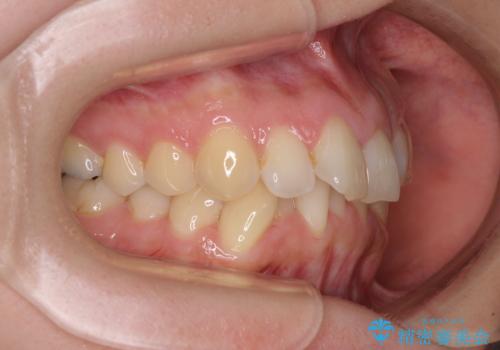

- 前歯のデコボコで前方に出ていることを気にして来院された患者様です。

上顎前歯が捻れて前方に飛び出しており、下顎前歯もそれに沿うようにデコボコとなっていました。

IPR(歯と歯の間を削る処置)によりスペースを獲得して上下顎前歯のデコボコを改善し、飛び出している前歯が引っ込むように設定し、インビザラインにて矯正治療を行うこととしました。